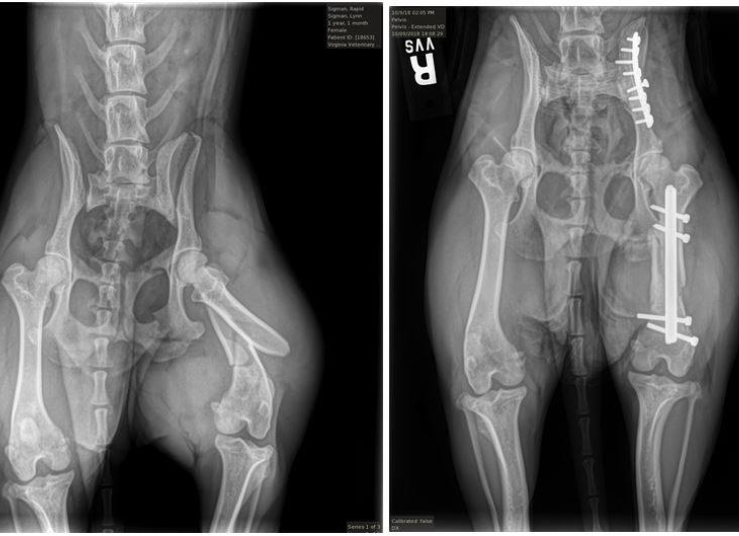

Our state-of-the-art radiology equipment produces clear, detailed images of your pet’s internal structures — including bones, joints, chest, and abdomen. These digital radiographs can detect fractures, foreign objects, tumors, heart or lung disease, and other abnormalities that might not be visible during a physical exam. Because the images are digital, results are available within minutes, enabling our team to begin diagnosis and treatment without delay.